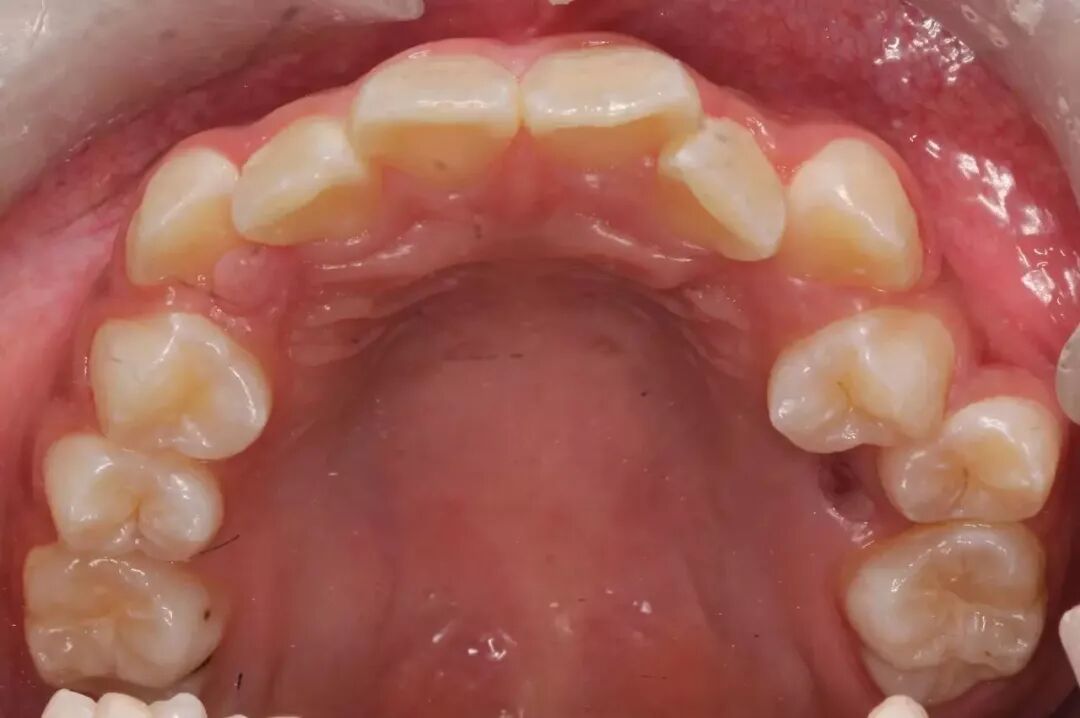

而上下颌骨就是牙齿的家,家的面积越来越小,导致人类的32颗牙齿不能很整齐的排成完美的弧形,而最直观的结果就是牙列拥挤、龅牙。

由于牙齿排列是不整齐的,那么在这种情况下硬性排齐牙齿,牙齿会“散出去”。

原来美美的侧貌反而被破坏,一说话的时候会感觉“满嘴都是牙齿”。

有好多小朋友牙齿不齐,在“虎牙”的位置。

这是由于“虎牙”是嘴巴里比较晚才长出来的牙齿,拥挤的情况下,往往都是这个最后长出的牙齿没有空间。

那么“虎牙”又是在嘴巴、面部美观起到关键作用的牙齿,它起到一个支撑口角的作用,并且支撑着面部的饱满度,并且保证微笑时候露出的前6颗牙齿是一个美美弧线,而不是死板的直线。